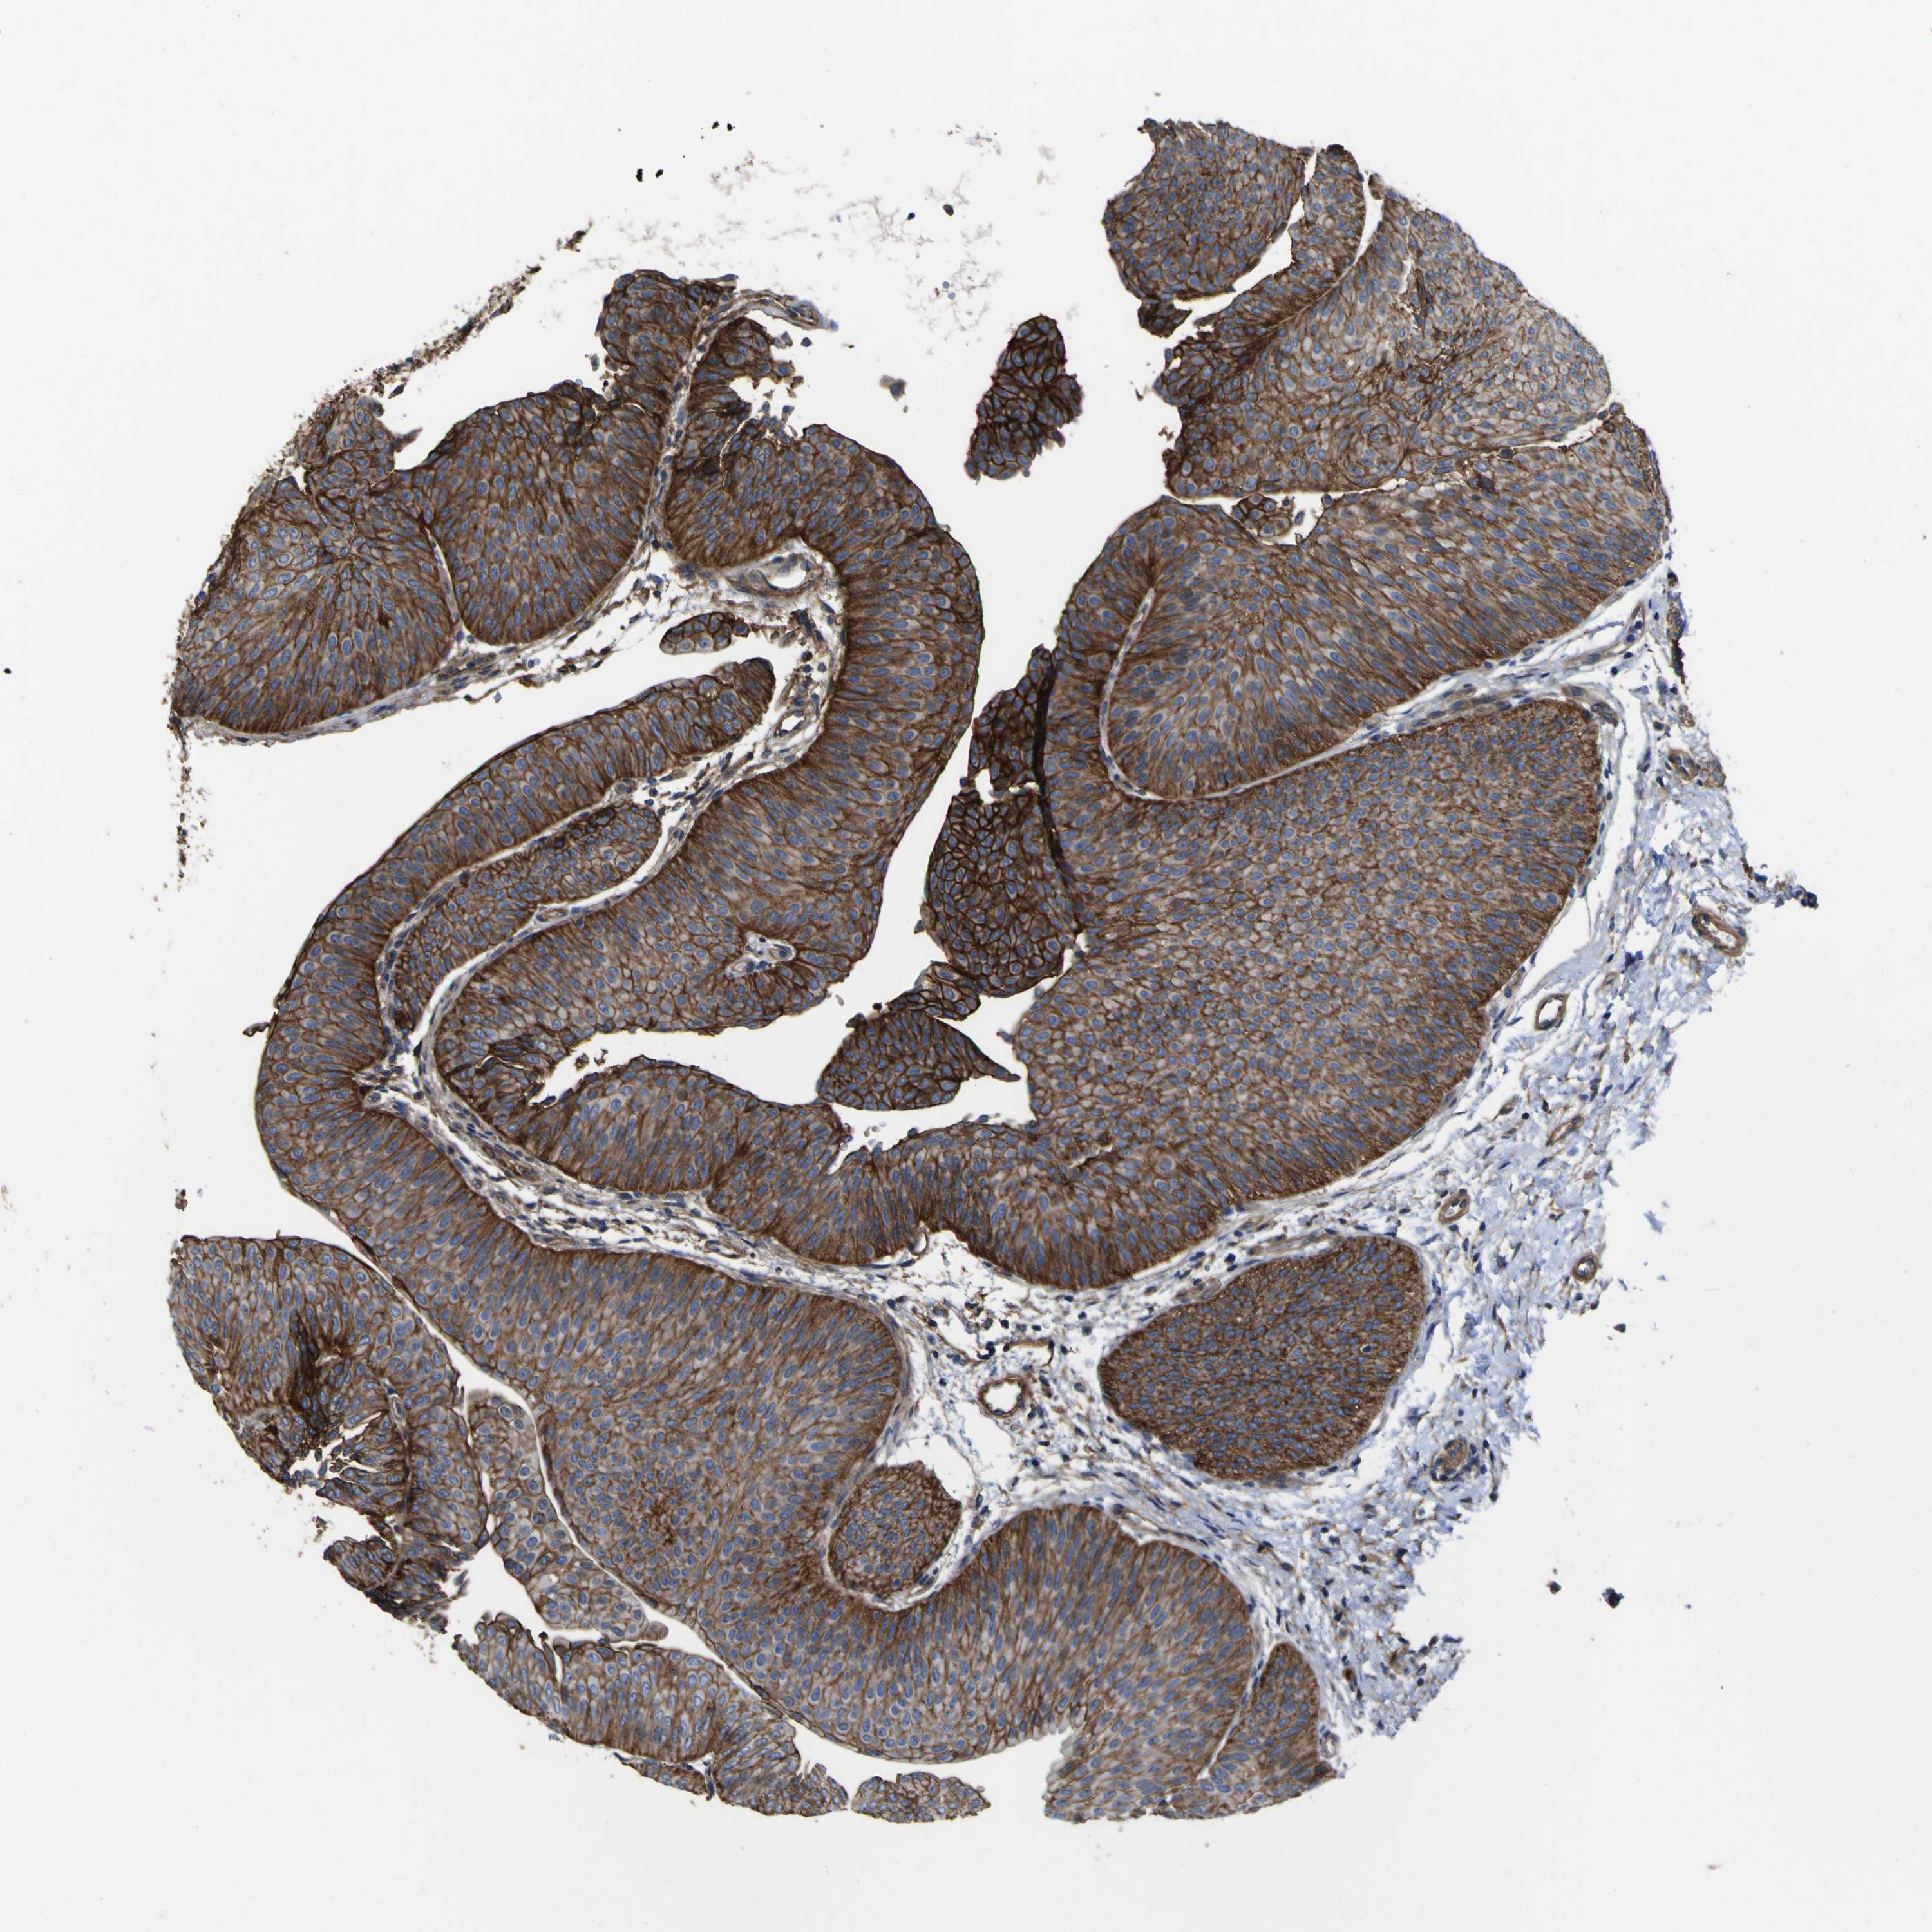

UROTHELIAL CANCER - Protein expressioni

A mouse-over function shows sample information and annotation data. Click on an image to view it in a full screen mode. Samples can be filtered based on level of antibody staining by selecting one or several of the following categories: high, medium, low and not detected. The assay and annotation is described here.

Note that samples used for immunohistochemistry by the Human Protein Atlas do not correspond to samples in the TCGA dataset.

Antibody stainingi

Antibody staining in the annotated cell types in the current human tissue is reported as not detected, low, medium, or high, based on conventional immunohistochemistry profiling in selected tissues. This score is based on the combination of the staining intensity and fraction of stained cells.

Each image is clickable and will lead to virtual microscopy that enables deeper exploration of all samples and also displays staining intensity scores, fraction scores and subcellular localization as well as patient and tissue information for each sample.

Antibody HPA011906

Antibody CAB002428

Urothelial carcinoma, Low grade

Urothelial carcinoma, High grade

Adenocarcinoma, NOS